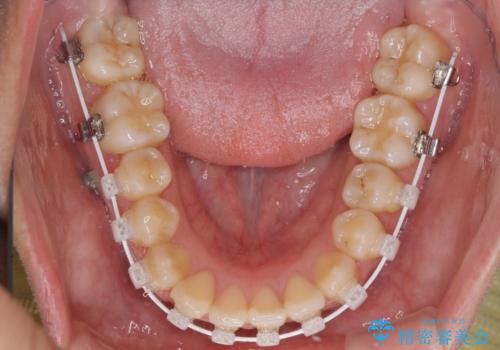

- 審美装置

受け口傾向の非抜歯矯正であったため、インビザラインによる矯正治療をお勧めしましたが、自己管理が面倒であるとのことで、ワイヤー装置にて行うこととしました。

右奥の歯が180度回転していることで、噛む度にワイヤーに無理な力がかかったようで、頻繁にワイヤーが切れてしまいました。また、下顎を後方に移動させるためのアンカースクリューも脱離することが多く、治療期間が長くなってしまいました。